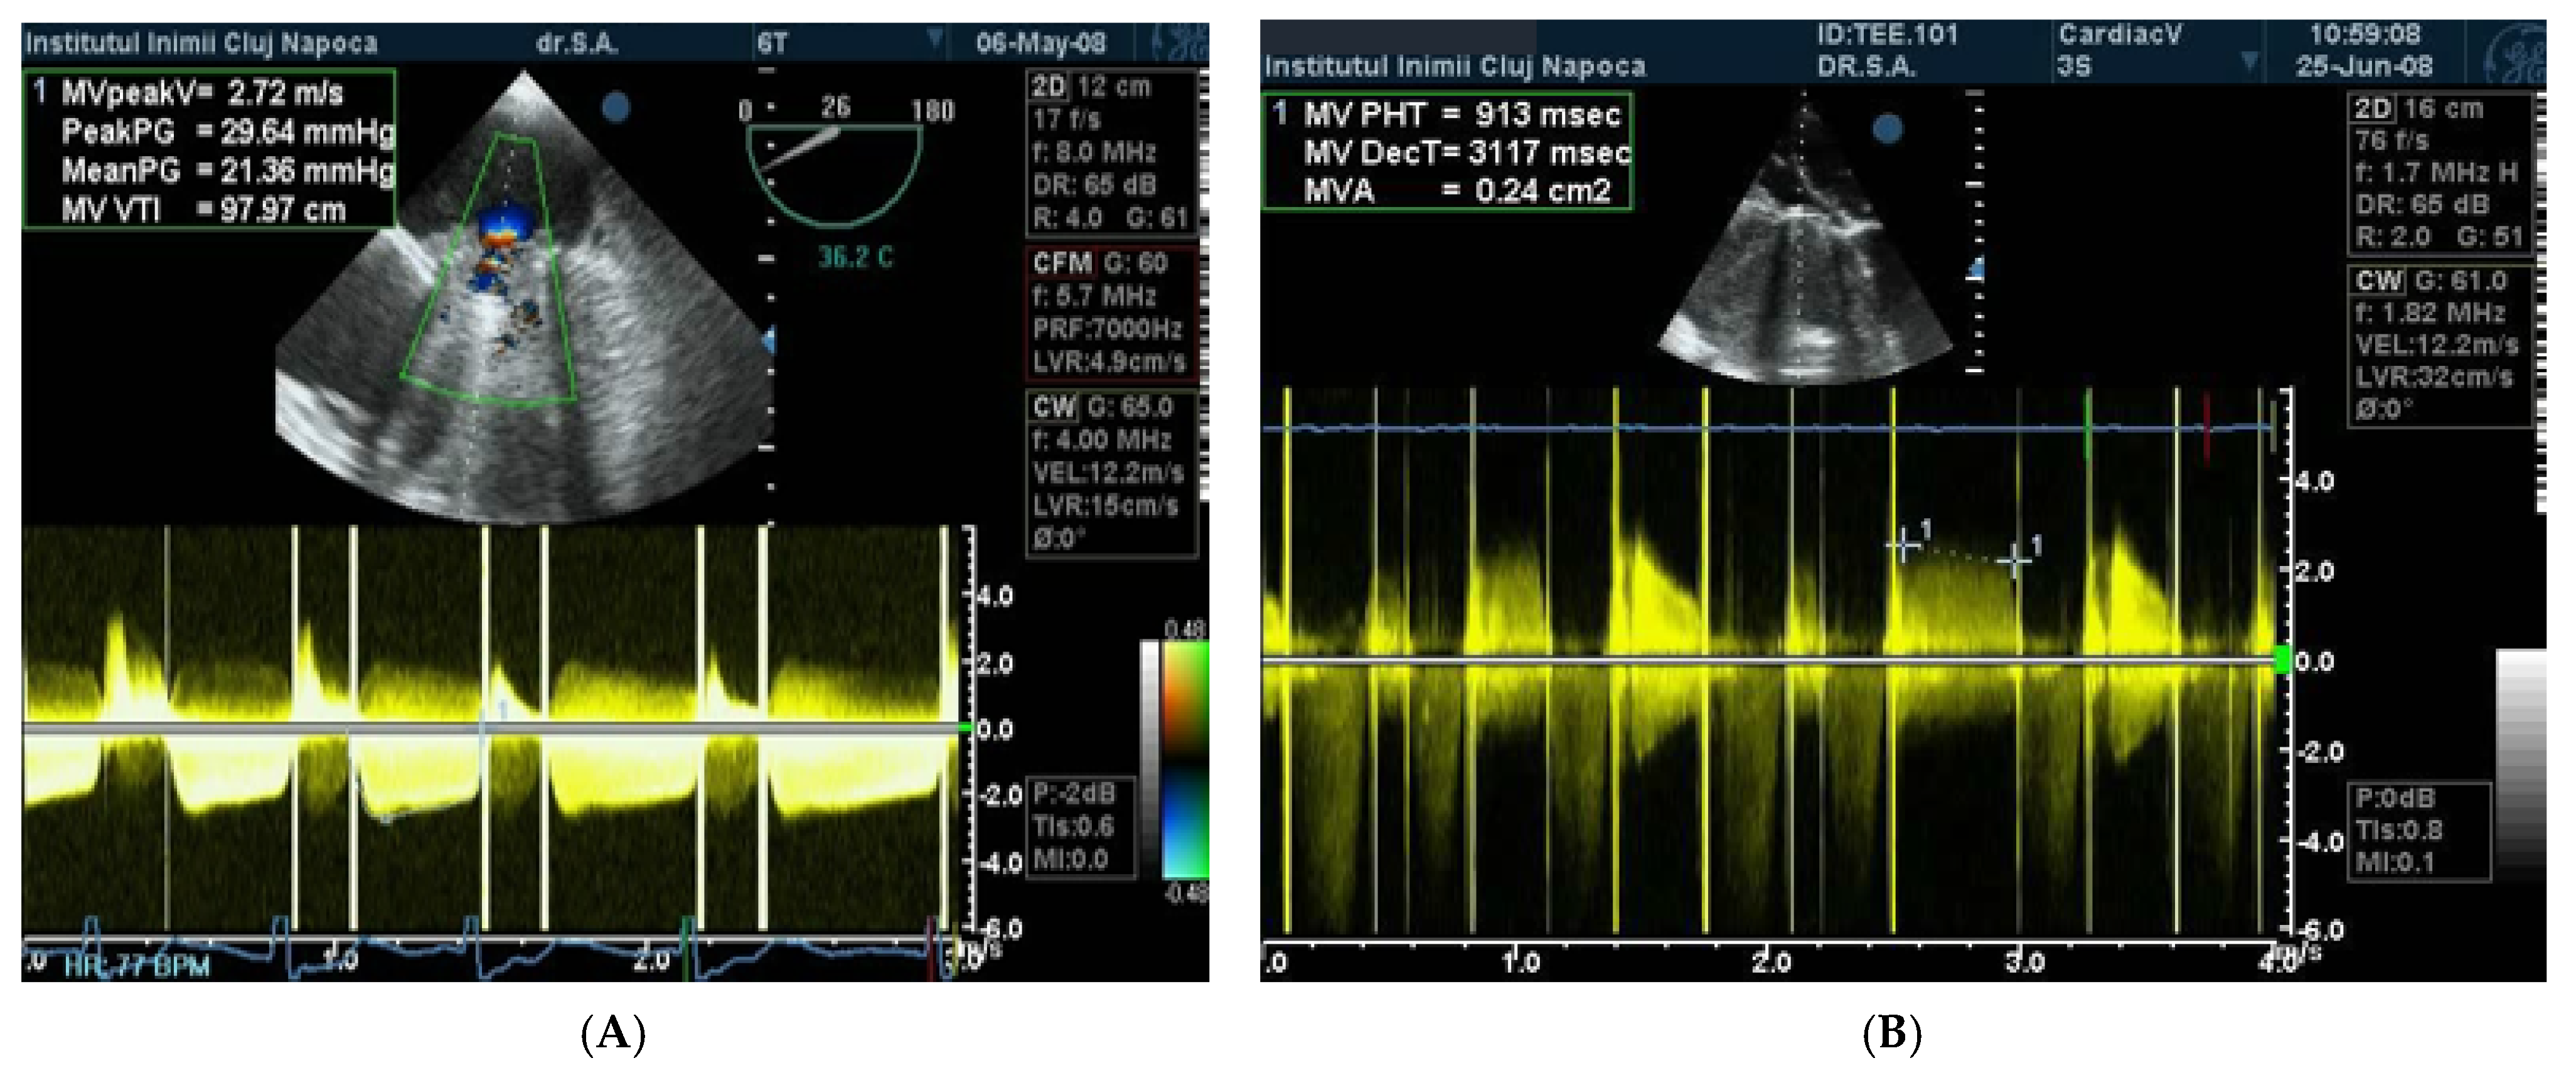

The echocardiographic criteria for obstruction are obtained using continuous Doppler (CW Doppler) quantification (Figure 1); mitral prosthesis obstruction is certain if the pressure half time (PHT) value is over 200 ms, the Doppler velocity index (DVI) is over 2.2, and there is a restricted disc mobility [13].

Figure 1.

(A) TTE CW Doppler. Obstruction of mitral prosthesis PHT > 200 ms. (B) TEE CW Doppler. High gradients and velocities on mitral mechanical prosthesis are suggestive for obstruction.